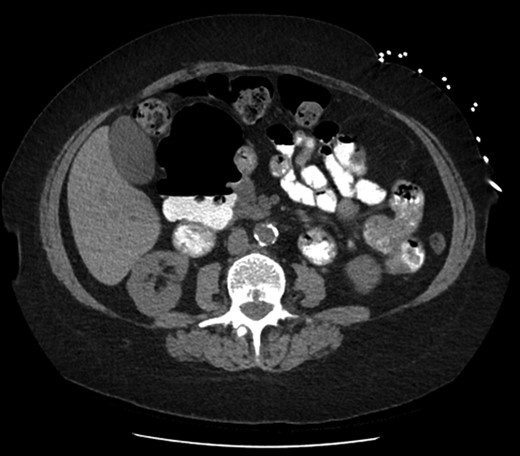

On examination she was afebrile, with observations within the normal parameters. Her abdomen was tender with voluntary guarding in the epigastrium. Her initial blood tests were all normal other than mildly increased inflammatory markers. She underwent a non-contrast (due to chronic kidney disease) Computed Tomography (CT) scan that revealed no evidence of acute biliary/gallbladder disease, however there was the appearance of a large duodenal diverticulum. The patient was recalled for an oral contrast study that confirmed a giant duodenal diverticulum arising from the second/third part of the duodenum measuring 9.5 × 5.7 × 7.3 cm. There were no signs of surrounding inflammation or pending rupture and this was thought to be an incidental finding. Upper abdominal ultrasound revealed no acute biliary tract disease. Her pain settled and she was discharged home.

On retrospective analysis of prior scans (CT and Magnetic Resonance Imaging (MRI)) of this woman there was evidence of this duodenal diverticulum for over five years and previous OGD three years prior had noted two duodenal diverticula; one small and one large. The patient denied previous knowledge of these findings (Fig 1 and 2).

Axial slice of computed tomography (CT) scan—giant diverticulum with air-fluid level containing oral contrast.